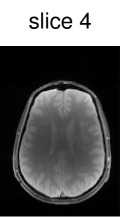

To verify the in-vivo applicability, human brain images of a healthy volunteer were acquired using the above described GRE sequence modified to include the optimized CAIPIRINHA-based pulses. The sequence parameters were set to , , bandwidth , matrix size and FOV . After acquisition, the k-space data of the individual slices were separated using an offline slice-GRAPPA ( coils, kernel size of ) reconstruction [42, 9]. The reference scans used in the slice-GRAPPA reconstruction were performed with the same sequence using an optimized single-slice pulse (not shown here). To decrease the scanning time, we acquired k-space lines ( of the full dataset) around the k-space center for each reference scan. After this separation, a conventional Cartesian reconstruction was performed individually for each slice.

Figure 6 shows the image reconstruction using optimized RF pulses for simultaneous excitation of two, four and six slices with the same slice separation and thickness as above. As can be seen clearly in the first column, all three pulses lead to the desired excitation pattern in-vivo as well. The remaining columns show the slice-GRAPPA reconstructions, which illustrate that the excitation is uniform across the field of view.